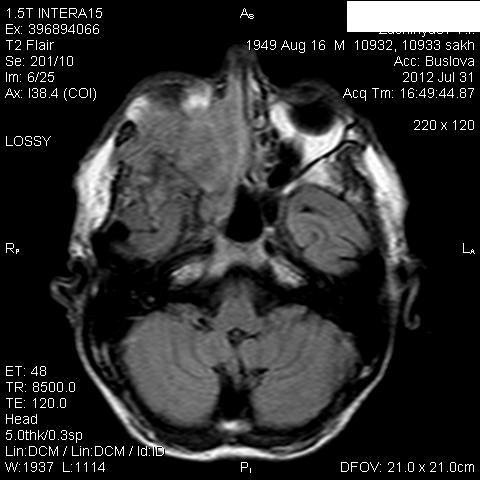

Мужчина лечился около месяца от правостороннего гайморита.Неоднократно пунктировали.Выписался из стационара, через 3 дня попал к другому ЛОР-врачу, который направил пациента на КТ, но волею судеб он оказался у нас.Визуально: незначительный экзофтальм справа, отек скуловой области, который периодически исчезает.Пыталась добыть его рентгеновский снимок пазух через знакомого отоларинголога, вхожего в лечебное учреждение, где лечился пациент-бесперспективно ( просто исчез, со слов лечащего врача-обычный правосторонний гайморит), хотя просила всего-то для себя, чтобы самой в такую ситуацию не попасть.

В заключение выставила объем.

Где-то в душе грелась мысль о нагноившейся гематоме, пока не показала исследование нашему отоларингологу, который пытался помочь в поиске рентгенограммы.

Нашла похожее образование в книге Г.Труфанова как плоскоклеточный рак.

Вот буквально две недели назад у нас был почти аналогичный пациент , он тоже длительно ходил по врачам и лечился прогреваниями от стреляющих в висок болей. Пришел на МРТ случайно -отправила к ЛОР и челюстно-лицевым хирургам. Думаю и здесь есть озлокачествление хронического процесса. Трудно сказать есть ли деструкция медиальной стенки пазухи , деформация точно есть.